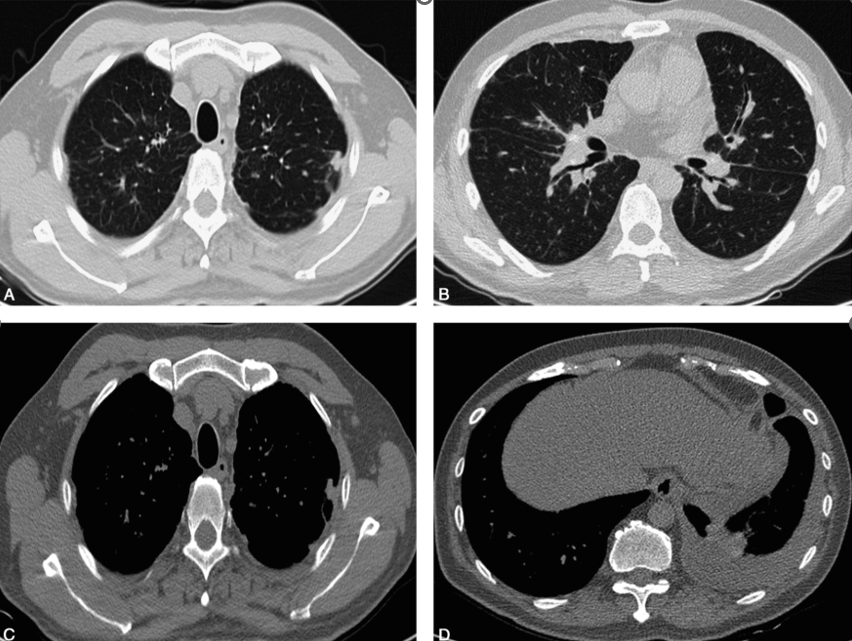

胸部CT平扫(2017-04-28,图1):双肺肺门及支气管血管束中央间质增生,小叶间隔增厚,双侧肺野弥漫性细小结节影;双侧胸膜局限性增厚及多发结节影;左侧少-中量胸腔积液;冠脉支架植入术后;心包少量积液。

图1胸部CT平扫:肺窗(A、B)示双肺弥漫细小结节影,小叶间隔增厚,中央间质增生;双上肺胸膜下结节影,以左上肺为著;纵隔窗(C、D)示左侧胸膜不规则增厚伴结节影,左侧少-中量胸腔积液